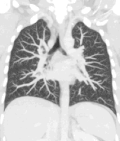

A CT scan can be used for detecting both acute and chronic changes in the lung parenchyma, the tissue of the lungs.[66] It is particularly relevant here because normal two-dimensional X-rays do not show such defects. A variety of techniques are used, depending on the suspected abnormality. For evaluation of chronic interstitial processes such as emphysema, and fibrosis,[67] thin sections with high spatial frequency reconstructions are used; often scans are performed both on inspiration and expiration. This special technique is called high resolution CT that produces a sampling of the lung, and not continuous images.[68]

Computed tomography angiography (CTA) is a type of contrast CT to visualize the arteries and veins throughout the body.[111] This ranges from arteries serving the brain to those bringing blood to the lungs, kidneys, arms and legs. An example of this type of exam is CT pulmonary angiogram (CTPA) used to diagnose pulmonary embolism (PE). It employs computed tomography and an iodine-based contrast agent to obtain an image of the pulmonary arteries.[112][113]